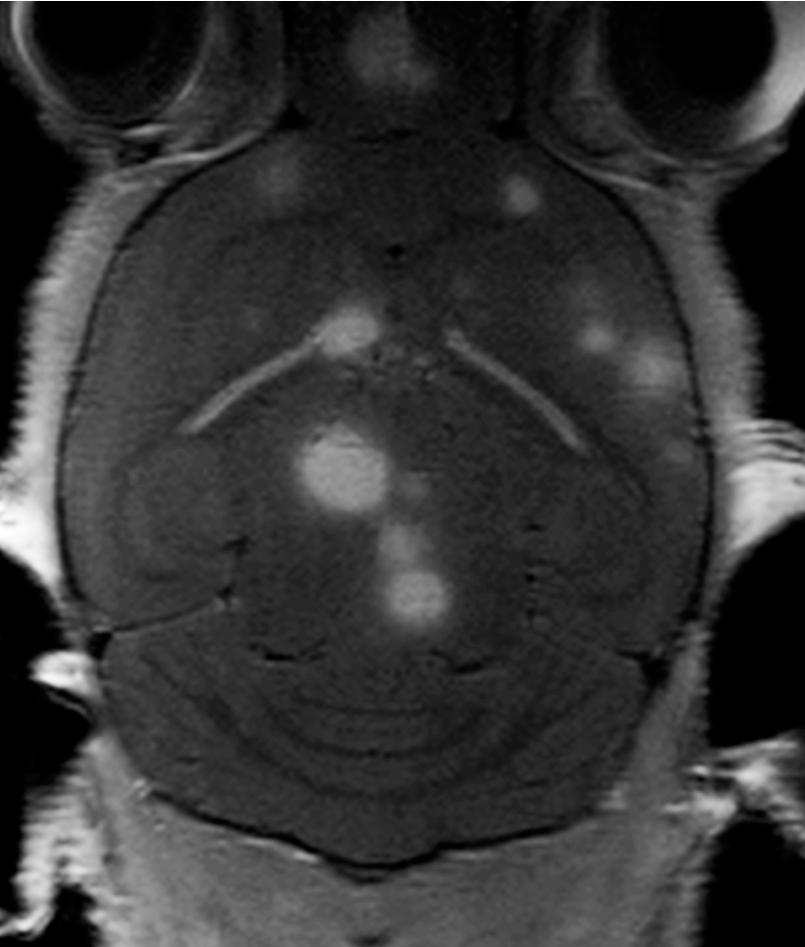

We have developed novel model systems in our lab, where human brain metastasis tumour cell lines from melanoma, lung cancer or human breast cancer are injected into the bloodstream of nod/scid mice. Through a highly standardized procedure, we inject the cell lines into the left cardiac ventricle in mice, and study tumour development by using multimodal, molecular imaging. During 3-6 weeks, all animals develop new tumours with a profound preference to the brain. MRI shows multiple metastases within the brain, similar to what is seen in patients (see figure). The models are thus among the very few which, in a systematic and consistent manner, can mimic the metastatic spread of cancers seen in patients.